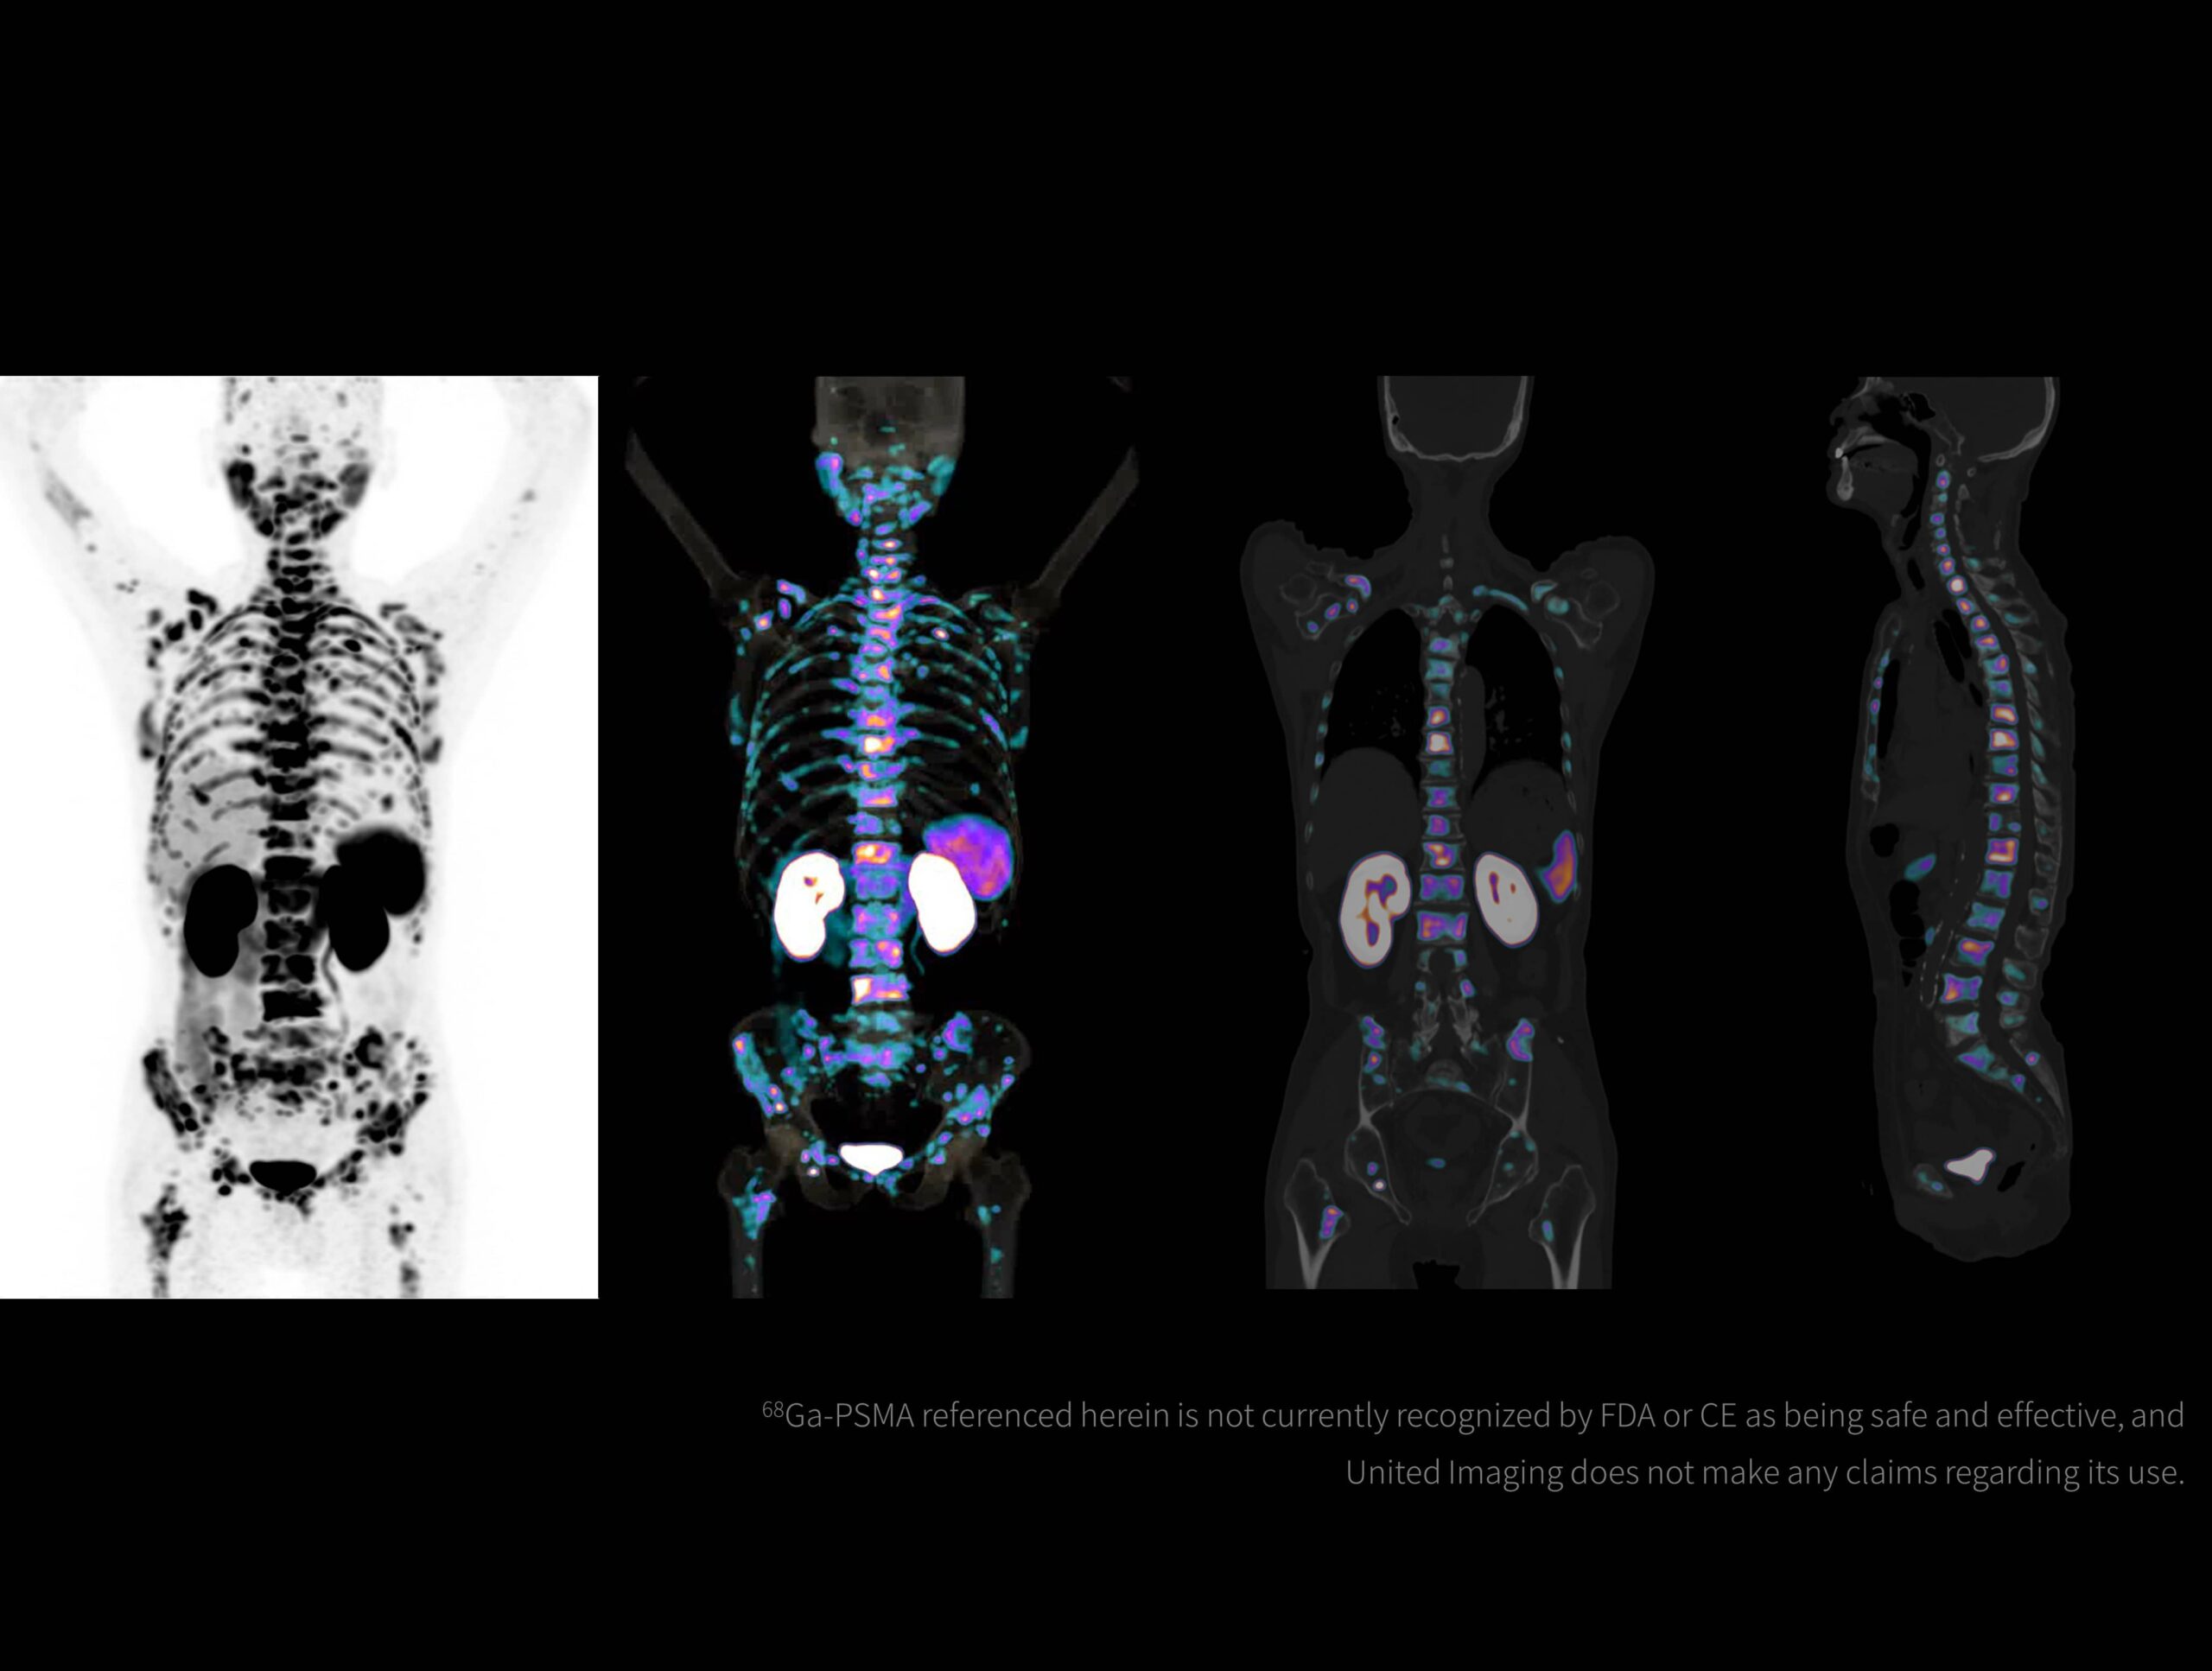

Imagistică de înaltă rezoluție obținută cu radiotrasor marcat cu galiu la doză redusă